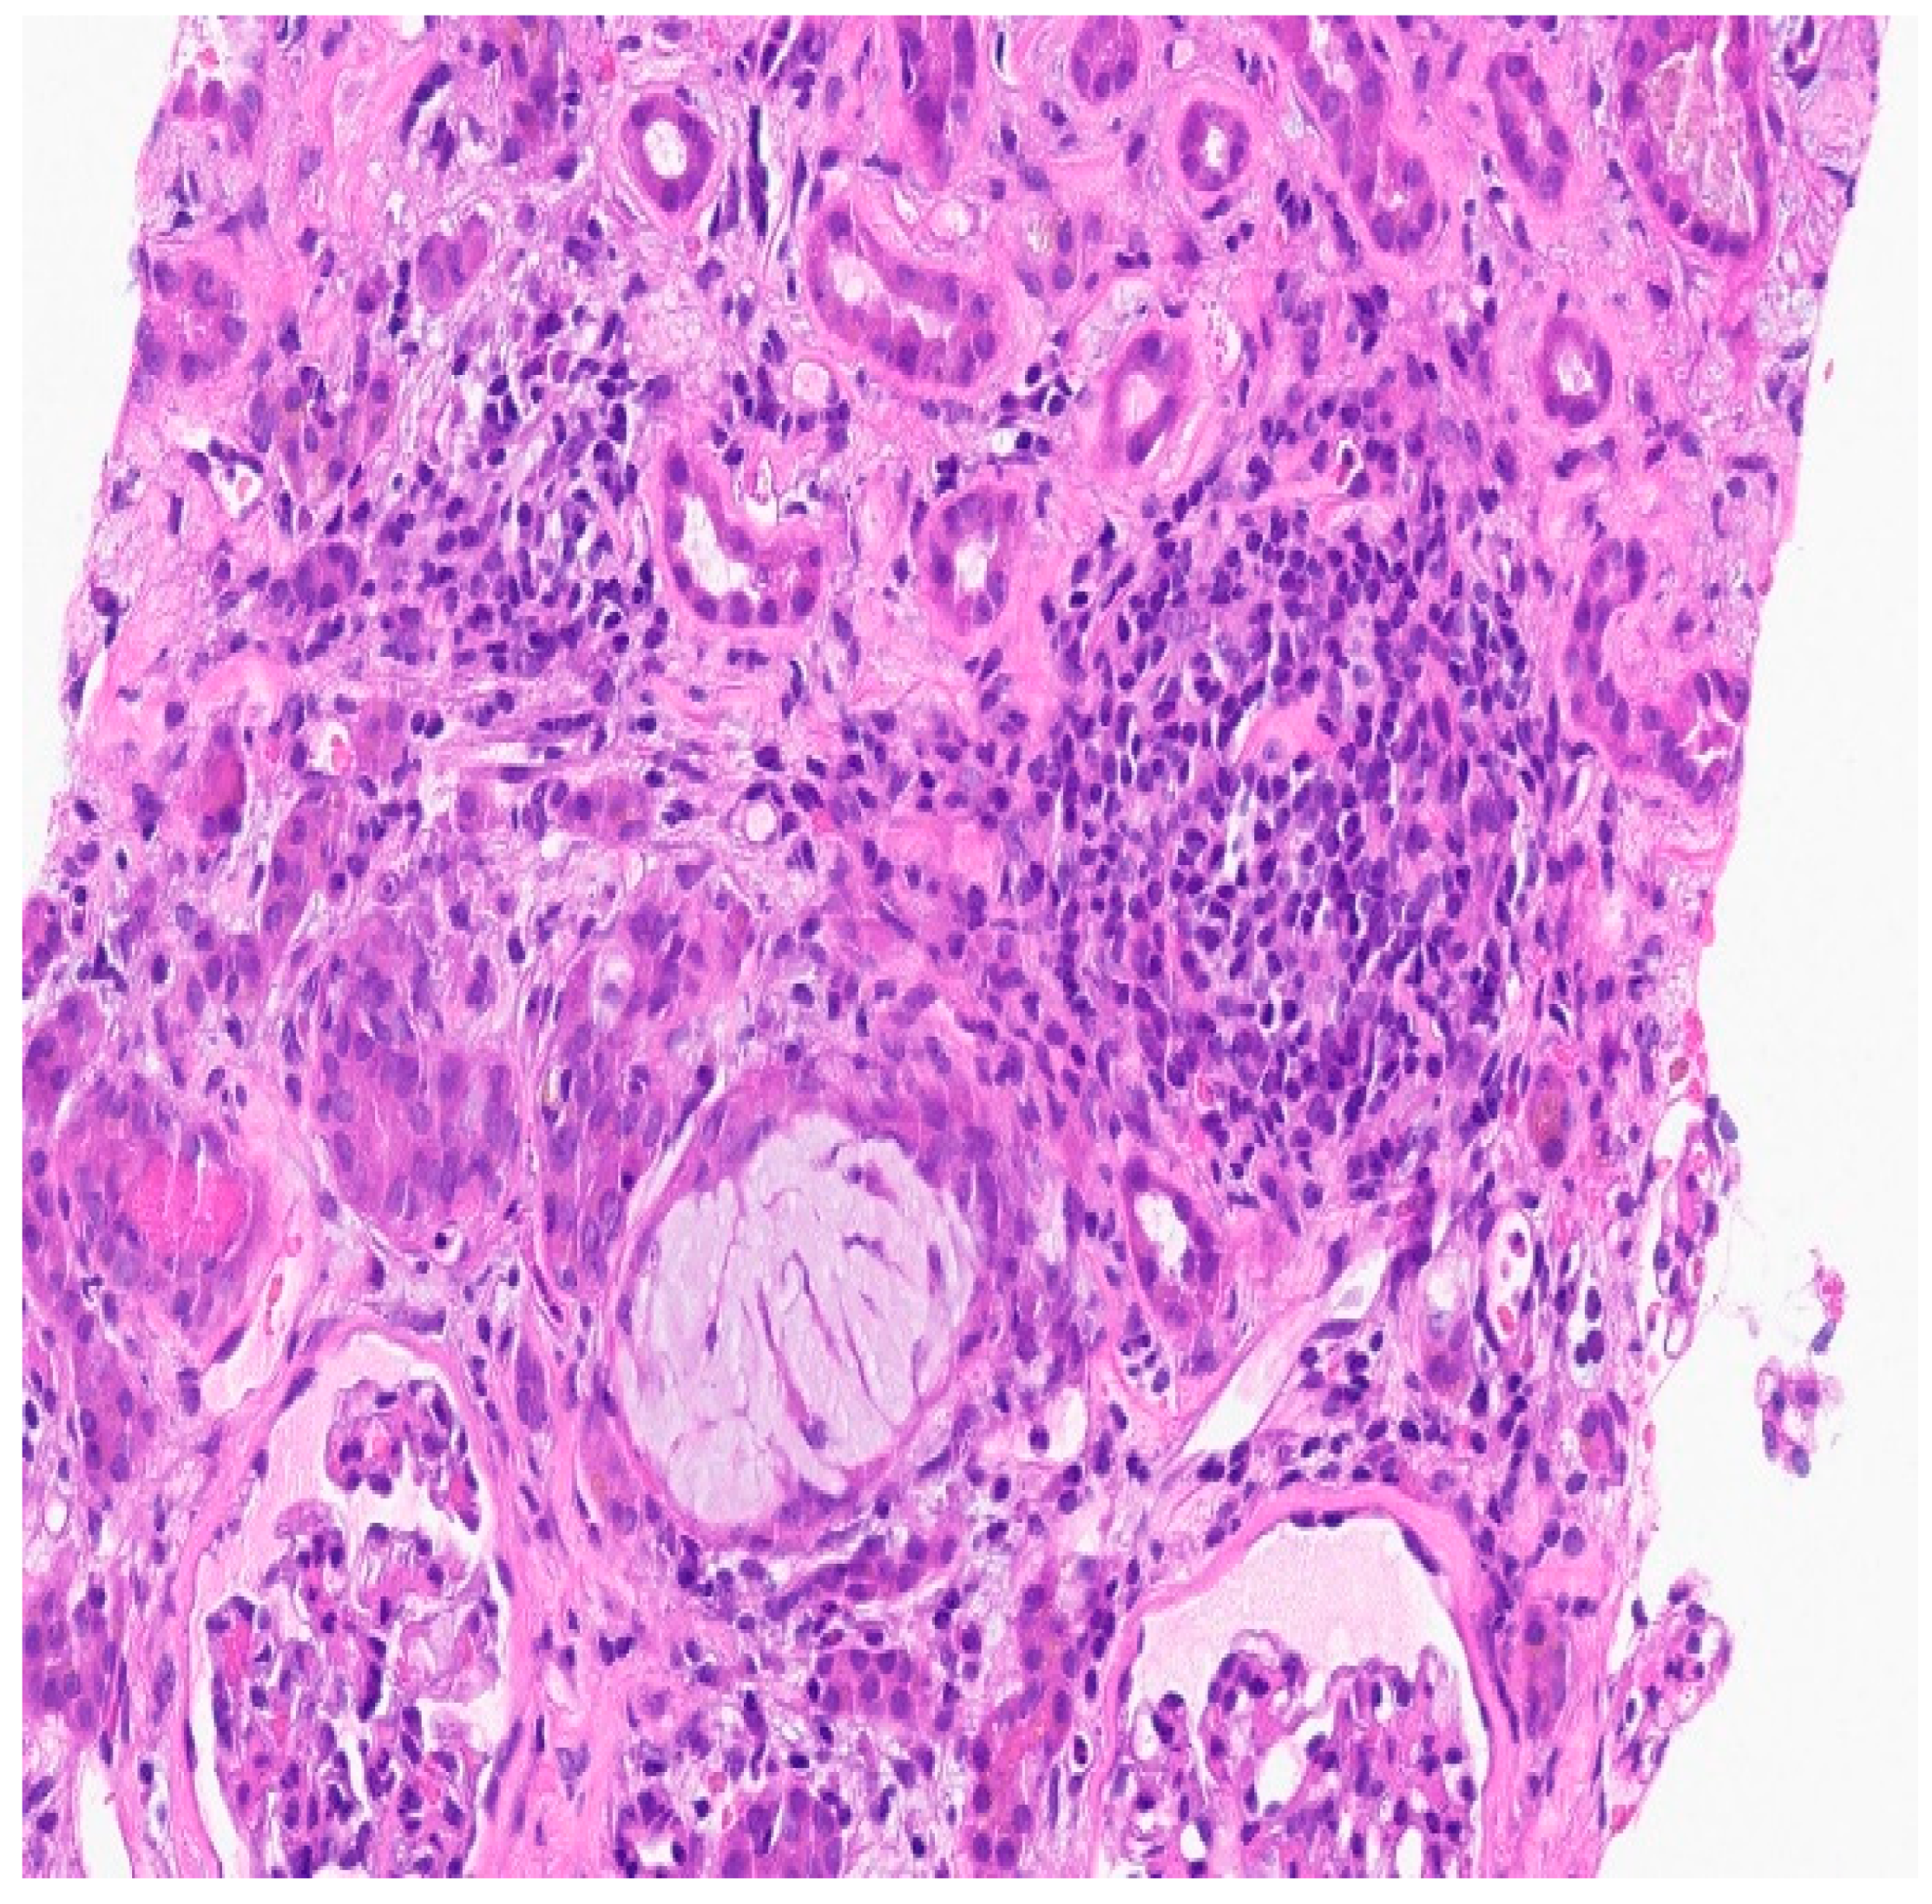

Figure 3. The background is inflammatory and there is an oxalate crystal in the center right. Necrotic debris in 2-3 tubules.

TUBULES AND INTERSTITIUM: There is severe diffuse interstitial edema involving cortex and medulla. There is severe tubular epithelial cell injury with luminal ectasia, fraying of the brush border, and simplification of the lining epithelium. Tubular lumina contain necrotic debris, and some lumina contain hyper eosinophilic ropy casts. The interstitium contains dense infiltrates of lymphocytes. Some areas contain aggregates of eosinophils. Mild tubulitis is seen. There are intratubular oxalate crystals (at least 3).

Impression: Kidney, needle biopsy: Acute interstitial nephritis.